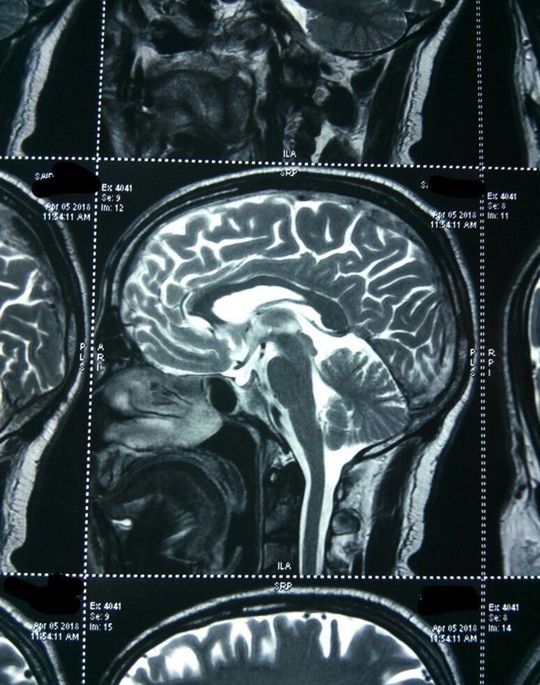

60 y male with 5 days history of progressively increasing severe holocranial headache . T2 MRI and contrast MRI shown

What is it??

Is it a thalamus tumor?